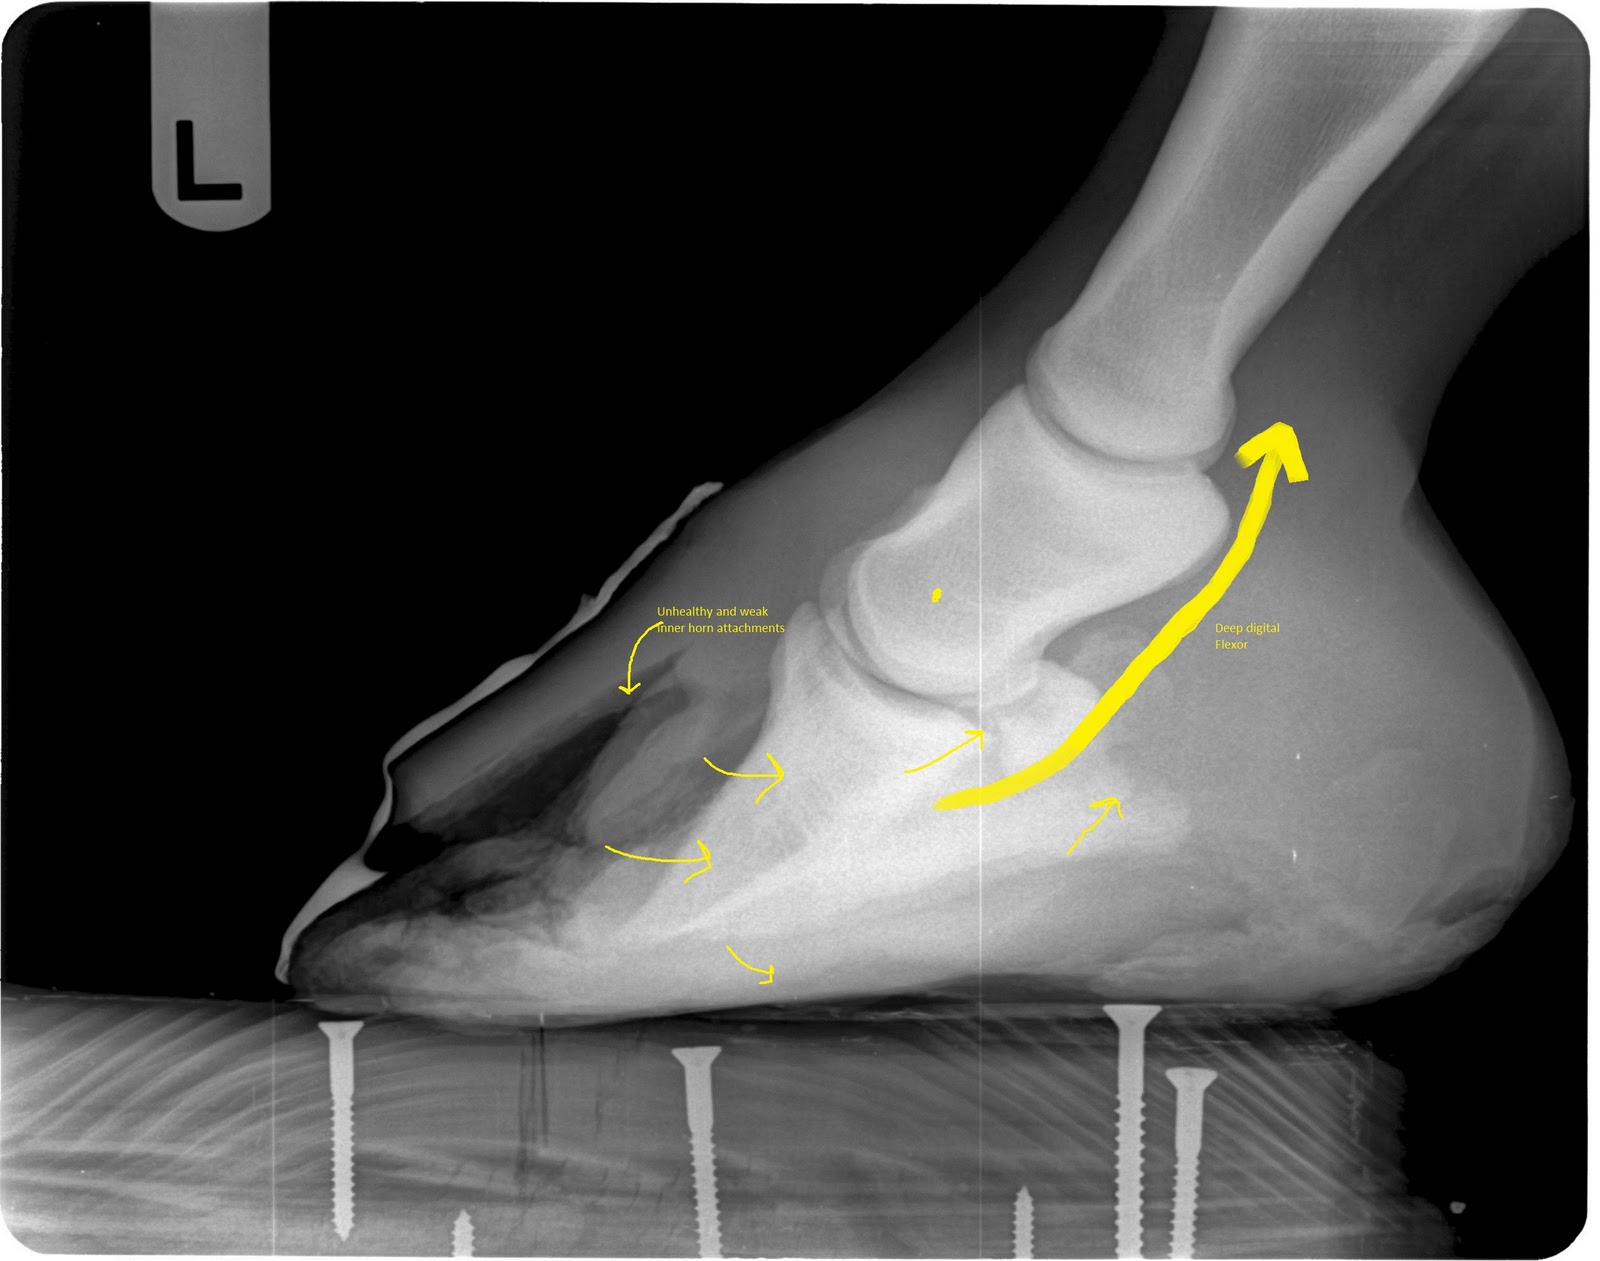

Innovative Equine Podiatry White line disease case study White Line Disease Zinc White line disease collectively refers to a group of lesions affecting the junction between the. white line disease in horses is a keratolytic condition affecting the deeper layers of the stratum medium of the hoof wall. In milder forms, wld does not cause lameness or any outward signs. what does wld do? what is white line disease/seedy. White Line Disease Zinc.